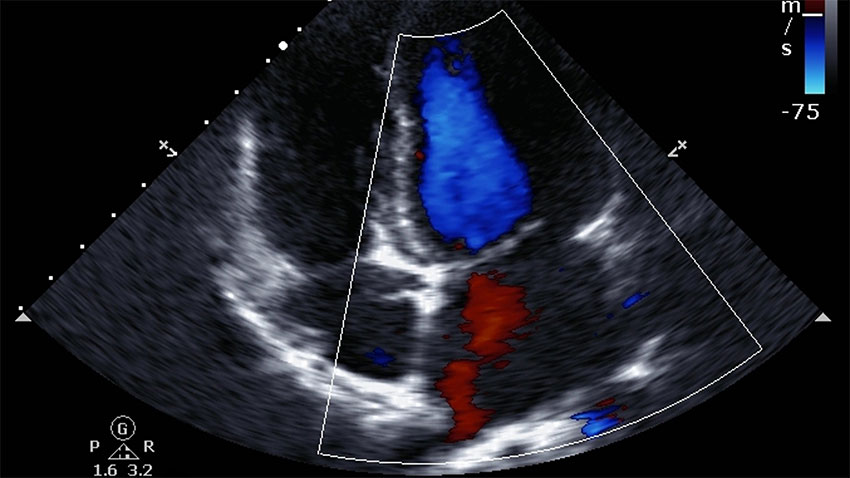

Explore Our Main Services

When you visit one of our state-of-the-art clinics we will make your examination as comfortable as possible with easy parking, spacious, private change rooms and comfortable waiting areas.